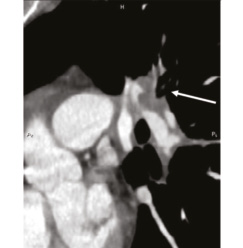

В 1993 г. на основании характерных признаков электрокардиограммы (ЭКГ) при профилактическом обследовании диагностирован феномен Вольфа–Паркинсона–Уайта. Клинических проявлений, снижающих качество жизни, пациентка не отмечала. К врачам далее не обращалась. В связи с появлением в 2015 г. одышки, перебоев в работе сердца, сердцебиения наблюдалась у участкового терапевта с диагнозом: ишемическая болезнь сердца, гипертоническая болезнь. Эхокардиография (ЭхоКГ), нагрузочные тесты не проводились. На фоне приема лозартана 25 мг/сут достигнуты целевые значения АД. В январе 2017 г. в связи с зарегистрированным на ЭКГ пароксизмом тахикардии с узкими комплексами QRS пациентка в порядке скорой помощи поступила с диагнозом «пароксизмальная суправентрикулярная тахикардия» в ЦРБ, где ритм был медикаментозно восстановлен. Далее в краевой больнице проведено внутрисердечное электрофизиологическое исследование и по его результатам – радиочастотная аблация дополнительных проводящих путей. Послеоперационный период протекал без осложнений. Однако в июне 2017 г. вновь появилась одышка при выполнении привычного объема физической нагрузки. По данным ЭКГ и рентгенограммы органов грудной клетки патологии не выявлено. Вскоре появилось кровохарканье (в течение 3 дней), и пациентка была направлена к фтизиатру, которым исключен туберкулез легких. 27.07.2017 на фоне значительного усиления одышки, выраженной тахикардии она потеряла сознание и в порядке скорой помощи доставлена в дежурный стационар, где травматологом и неврологом исключены сотрясение головного мозга и закрытая черепно-мозговая травма. Пациентка отпущена домой. В связи с сохраняющейся одышкой при подъеме на один лестничный пролет в августе 2017 г. по собственной инициативе она обратилась к кардиологу. При проведении ЭхоКГ выявлены увеличение правых камер сердца и признаки их объемной перегрузки. С предварительным диагнозом ТЭЛА пациентка направлена в дежурный стационар, где в экстренном порядке проведена спиральная компьютерная томография (СКТ) с контрастированием легочной артерии. Выявлены признаки легочной тромбоэмболии крупных и средних ветвей легочной артерии (ЛА) с обеих сторон (рис. 1–4). При целенаправленном сборе анамнеза выяснилось, что в течение 3 лет (с 2014 г.) пациентка принимает Линдинет 20 мг – монофазный пероральный контрацептив (этинилэстрадиол + гестоден), назначенный гинекологом с целью контрацепции. По данным ультразвукового исследования вен нижних конечностей выявлен тромбоз суральных вен справа. Линдинет отменен. На фоне лечения антикоагулянтами (гепарин, эноксапарин) состояние женщины несколько улучшилось. Она переведена на варфарин, который далее заменен на апиксабан в дозе 10 мг 2 раза в день.

Рис. 1: а – тромбы в верхнедолевой ветви левой ЛА; б – верхнедолевая ветвь левой ЛА проходима. | |

Рис. 2: а – тромбы в правой ЛА и нижнедолевой ветви левой ЛА; б – правая ЛА и нижнедолевая ветвь левой ЛА проходимы. | |

Рис. 3: а – тромбы в нижнедолевой ветви левой ЛА и нижнедолевой ветви правой ЛА; б – сохраняется тромбоз нижнедолевой ветви правой ЛА. | |

Рис. 4: а – тромбы в левой ЛА и ее ветвях; б – тромбоза левой ЛА (нисходящей ветви) не выявлено, сохраняется тромбоз нижнедолевой ветви левой ЛА. | |

По данным чресприщеводной ЭхоКГ тромбоза камер сердца не обнаружено, однако уровень D-димера – более 250 мкг/л. Исследования в отношении патологии гемостаза выявили значительный дефицит протеинов С и S. Проведена замена апиксабана на ривароксабан 15 мг 2 раза в сутки с последующим переводом на прием ривароксабана 20 мг 1 раз в сутки в связи с большей биодоступностью последнего. Также с целью усиления антитромботического эффекта к терапии добавлен клопидогрел в дозе 75 мг в сутки. При проведении СКТ органов грудной клетки с контрастированием легочной артерии 26.09.2018 выявлена положительная динамика (см. рис. 1, б, рис. 4). Состояние стабилизировалось, рецидивы одышки прекратились. От имплантации кава-фильтра пациентка отказалась.